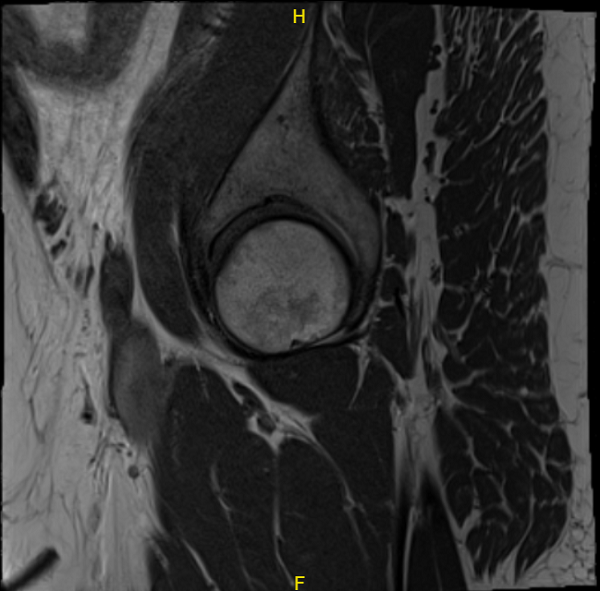

A 59-year-old patient visited our office with complaints regarding pain on the inner side of his right knee as well as outside of the right hip. We did the MRI of the hip and the knee, which showed medial root tear of the right knee and trochanteric bursitis of the right hip.

MRI Right knee non-contrast